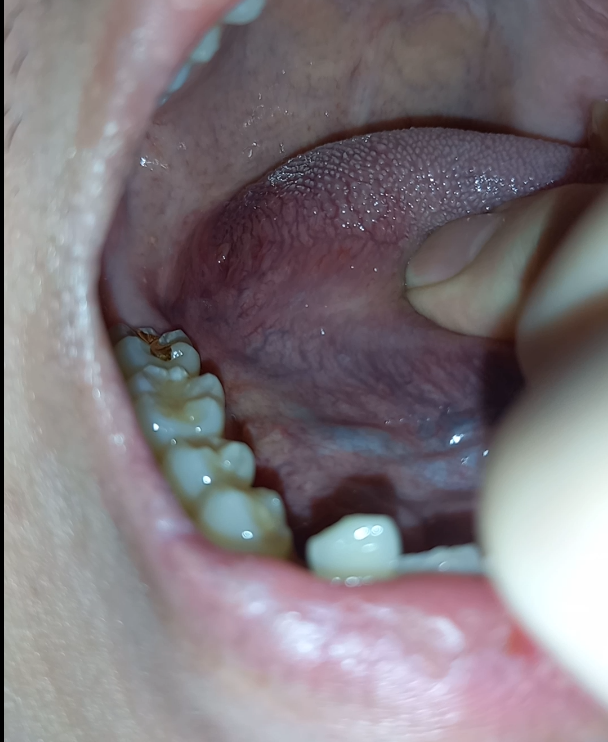

혀 측면 가장 안쪽 끝부분에 돌기같은게 있어요.

혀 측면 가장 안쪽으로 끝부분에 돌기같은게 나있는걸 발견하게 됐습니다.

혹시나 해서 반대편도 확인해보니 비슷한 돌기가 있더군요.

왼쪽 오른쪽 사진은 첨부해 두겠습니다.

돌기 위에 빨간 부위는 실핏줄같은거 같더라구요. 혀를 앞으로 당겨오니 보였습니다. 이것도 양쪽 다 보입니다.

양쪽에 보이는 돌기는 정상적인 구조물인건가요? 아님 치료가 필요한 건가요?

• 2번 째 사진

크기나 모양으로 봤을 때에는 점액낭종의 가능성은 있어보입니다. 지켜보시고 사라지지 않으면 치과 가보시면 됩니다.

사진으로 봤을 경우에는 큰 문제가 없어 보입니다. 구강 점막에는 가끔씩 점액종이라고 하는 것이 생기기도 합니다. 구강 점막이 과도한 자극에 의해서 마찰이 되면 내부의 조직액이 차에서 생기는 증상입니다. 크게 문제가 되진 않을 것으로 생각합니 됩니다. 자 자세한 확인을 위해서 치과에서 진료를 받아오세요.

사진에 보이는 돌기들은 정상적인 모습이고 첫번쨰 사진에 보이는건 물집이 잡힌거 같습니다. 큰 문제가 잇는건 아닙니다.